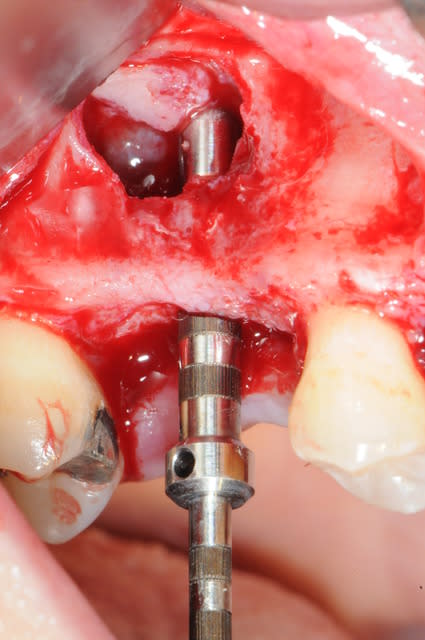

les suivantes;

- forage et transperçage de la crête sans aller trop loin...

- essayage pilier pour parallélisme

- forage à 3mm

- visualisation de la hauteur sous la membrane de Schneider

- utilisation d'un ostéotome diamètre 3.4 puis 3.8

(sous dimensionnement de diamètre par rapport à l'implant prévu :4mm)

- mise en place de l'implant

- séchage discret de la surface osseuse

- injection du Vital Os en palatin et partout autour de l'implant

- hé hé hé ... pas de membrane de recouvrement, le matériaux se suffit à lui même. d'où une petite économie substantielle pour ceux qui ont l'habitude de mettre systématiquement une membrane après un Caldwell-Luc.

- sutures...